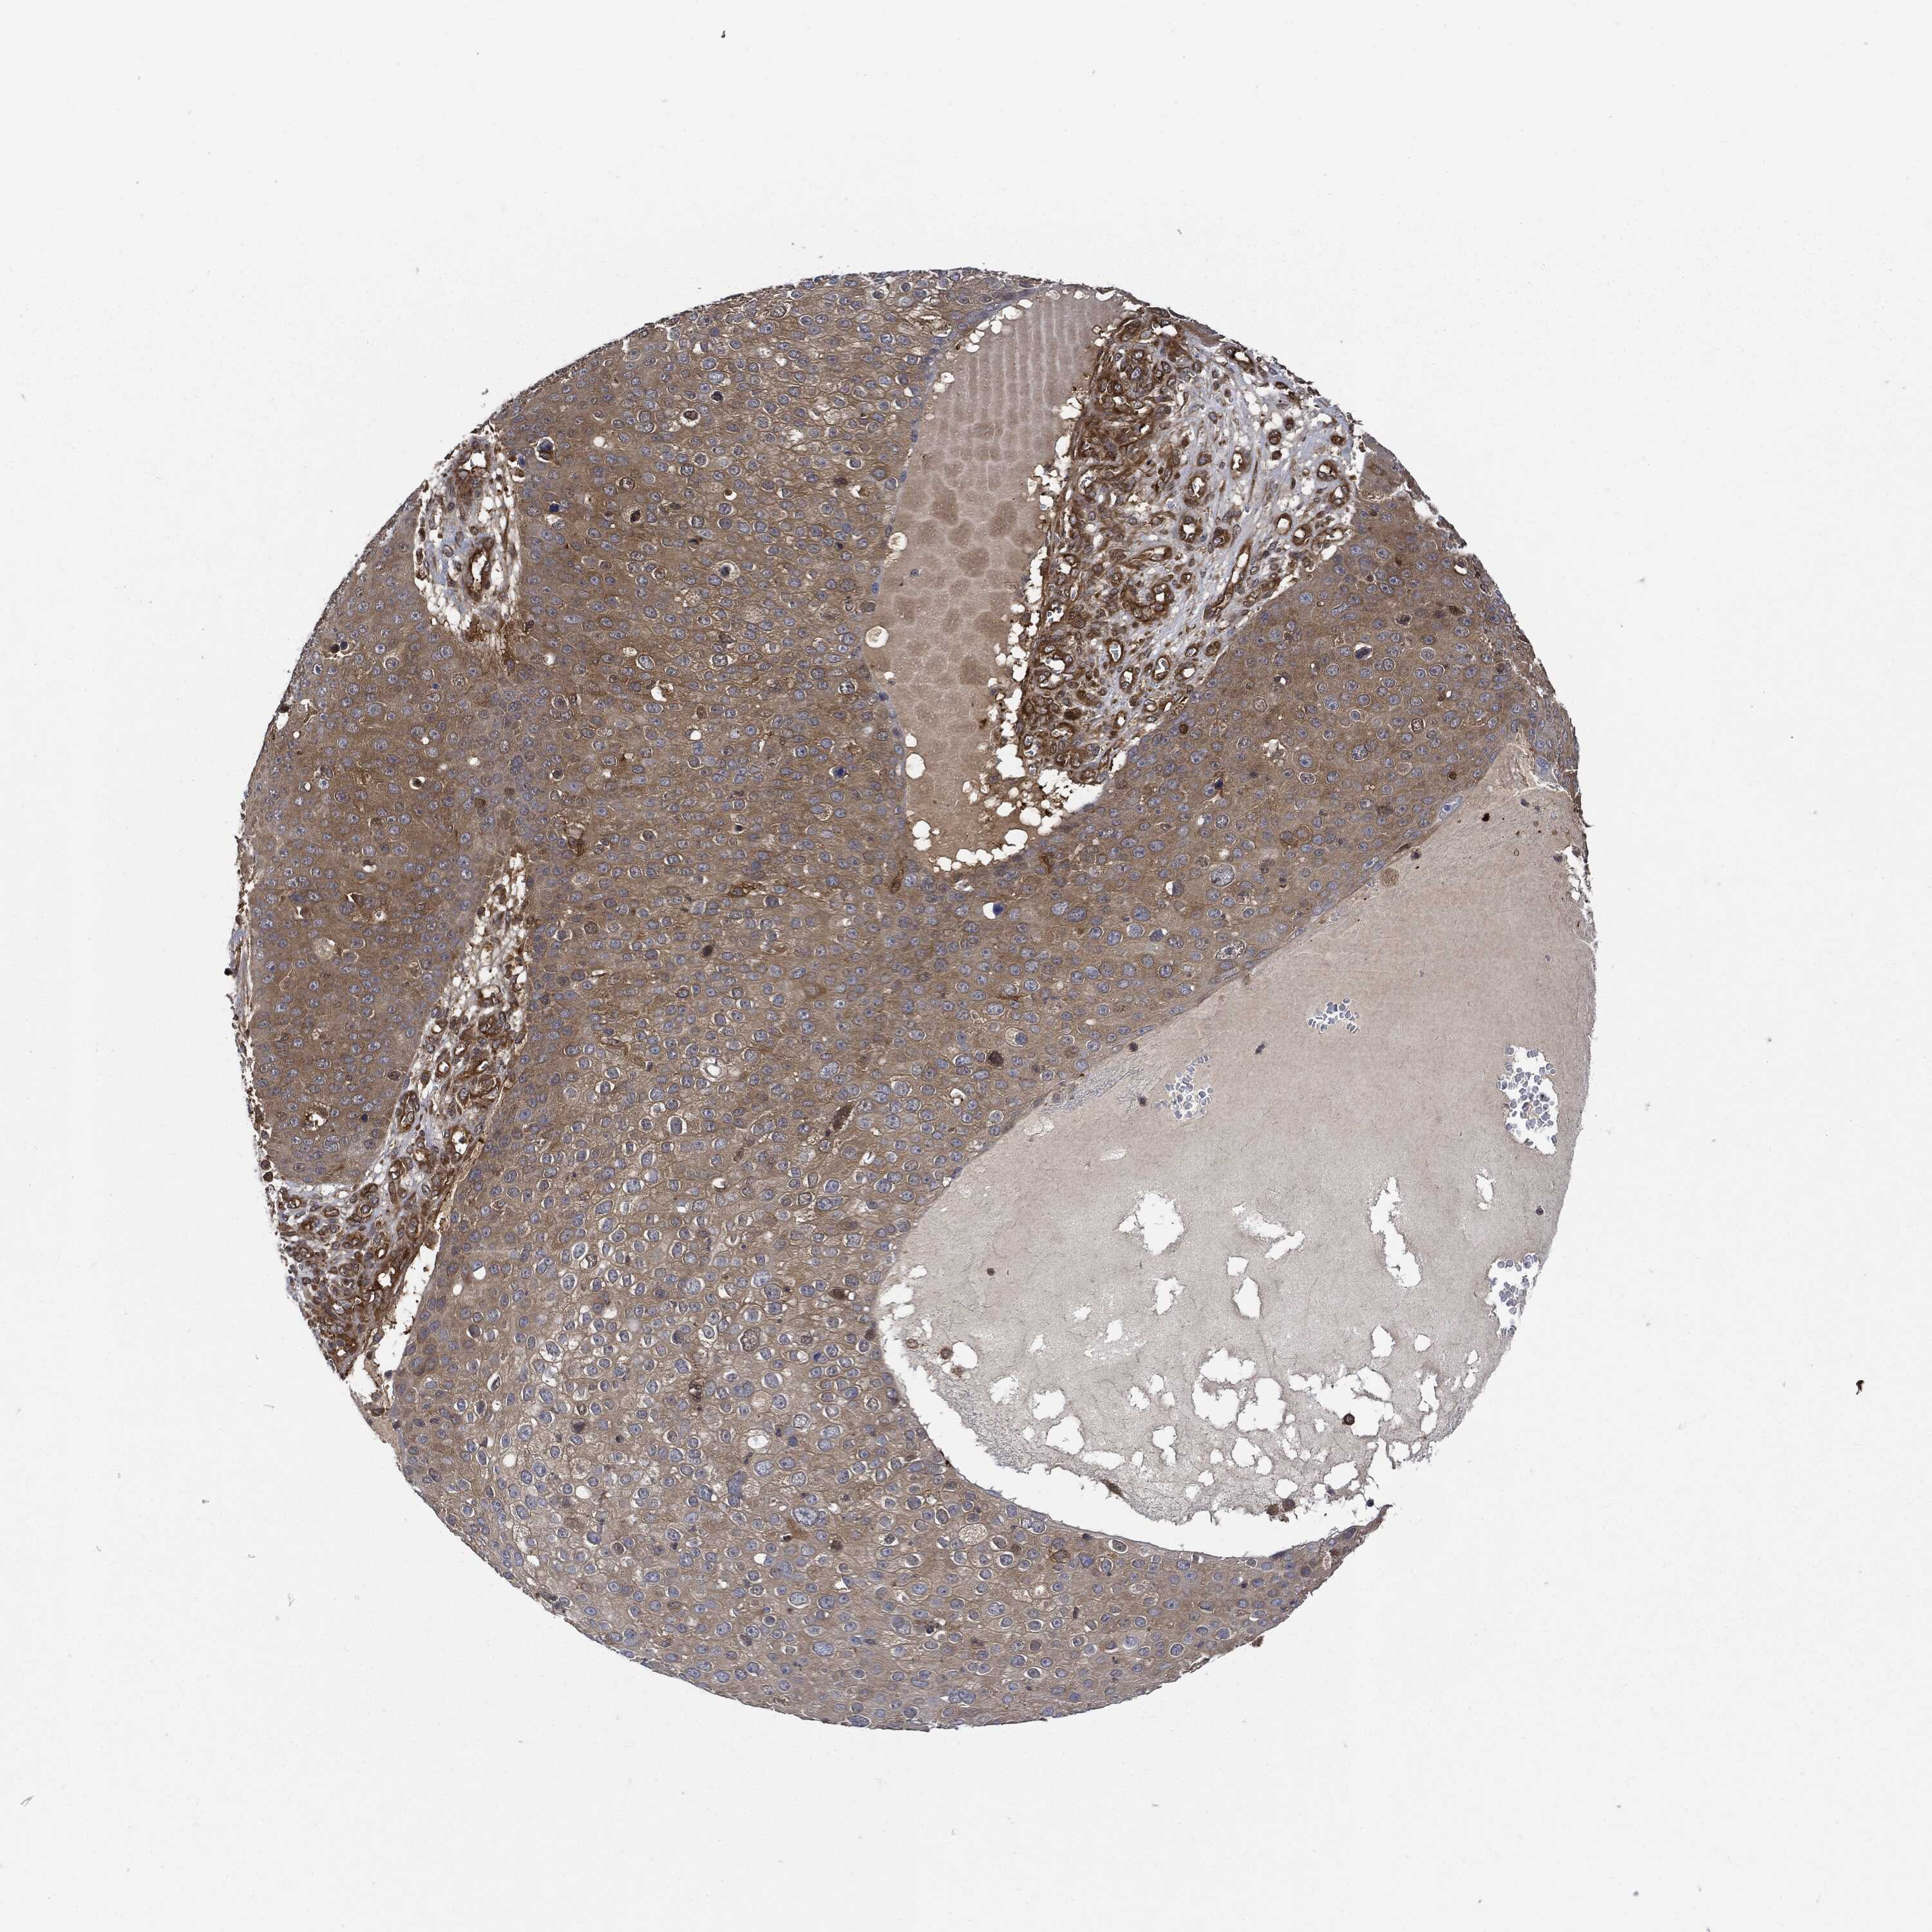

CANCER SKIN CANCER Show tissue menu

Basal cell and squamous cell cancer

SKIN CANCER - Protein expressioni

A mouse-over function shows sample information and annotation data. Click on an image to view it in a full screen mode. Samples can be filtered based on level of antibody staining by selecting one or several of the following categories: high, medium, low and not detected. The assay and annotation is described here.

Each image is clickable and will lead to virtual microscopy that enables deeper exploration of all samples and also displays staining intensity scores, fraction scores and subcellular localization as well as patient and tissue information for each sample.

Basal cell carcinoma